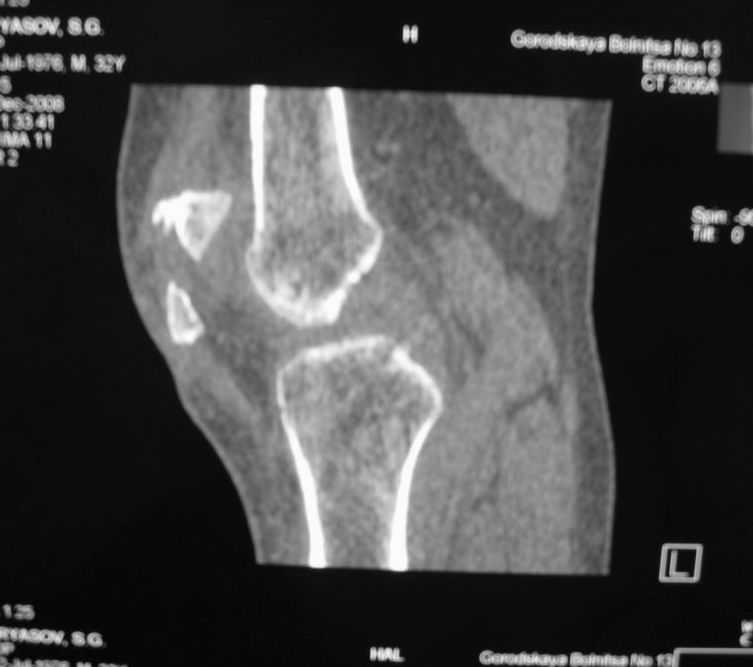

Уважаемые коллеги! Обратился пациент 32 лет с травмой коленного сустава от июля 2008 года - падение с мотоцикла, прямой удар передней поверхностью коленного сустава. Диагноз - открытый оскольчатый перелом надколенника. В одной из больниц города выполнили ПХО, шов надколенника лавсаном. Заживление раны с частичным нагноением(разведена на участке 3 см).

Сейчас мягкие ткани в порядке. R-снимки, КТ в приложении. Объем движений 0/0/110 гр.Ходит почти без хромоты.

Жалобы на торчащий под кожей один из отломков, боль в этой точке.Вопрос: что делать? Первое - убрать этот отломок и на этом закончить. Второе - оставить все как есть(отломок не так уж и сильно мешает). Ждать возможного развития артроза, дальше по ситуации. Третье - подумать о протезировании надколенника.